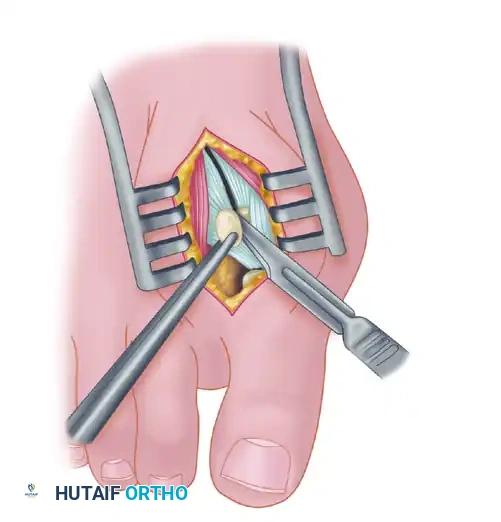

Fibular (Lateral) Sesamoidectomy: Plantar Approach

If the dorsal approach proves too difficult due to anatomical constraints, a plantar approach can be utilized for fibular sesamoidectomy.

- Have an assistant hold the ankle in dorsiflexion. A surgical headlight is highly recommended to visualize the full depth of the plantar wound.

- Flex and extend the hallux while palpating the plantar aspect of the foot to locate the sesamoid.

- Beginning 1.0 to 1.5 cm distal to the MTP joint, make a longitudinal incision on the plantar surface of the foot, extending proximally 3.5 to 4.0 cm between the first and second metatarsals.

- Separate the skin and fascial septa within the forefoot pad, and insert a small self-retaining retractor.

- Using small, blunt-tipped dissecting scissors, meticulously identify the neurovascular bundle to the first web space. Retract it laterally or medially, depending on the exact subluxated position of the sesamoid.

- Incise the plantar capsule and isolate the fibular sesamoid. Carefully shell it out from its soft tissue envelope, taking great care to protect the adjacent FHL tendon.